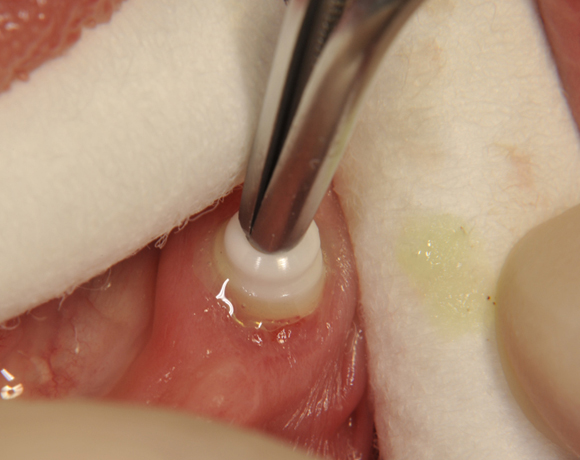

Bild 02: Reinigung der Klebeflächen an den Implantaten

Bild 03: Ausspülen der Klebeflächen mit H2O2